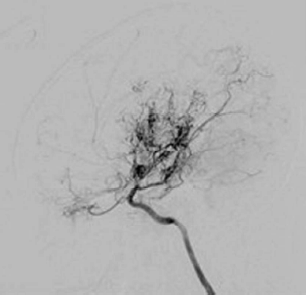

Um menino japonês de 6 anos apresenta perda de força do lado esquerdo ao acordar e é encontrado por sua mãe, que rapidamente liga para o SAMU. No departamento de emergência, seu exame demonstra uma hemiparesia esquerda, juntamente com hemianopsia homônima à direita. Uma imagem de ressonância magnética revela um acidente vascular cerebral e a angiografia cerebral digital é mostrada. Em relação a essa condição, é correto afirmar que